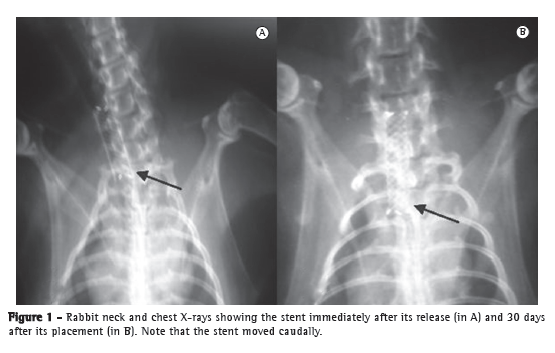

Stent migration was observed in 5 of 6 animals (84%). Of the 13 animals that survived the observation period, 7 had rigor mortis, which precluded hyperextension of the neck for X-ray examination and, consequently, the determination of the exact position of the stents. Therefore, stent migration was analyzed in the 6 remaining animals only. Covered and self-expanding stents have been reported to show high migration rates, our results being therefore consistent with those reported in the literature (Figure 1).(6,7)